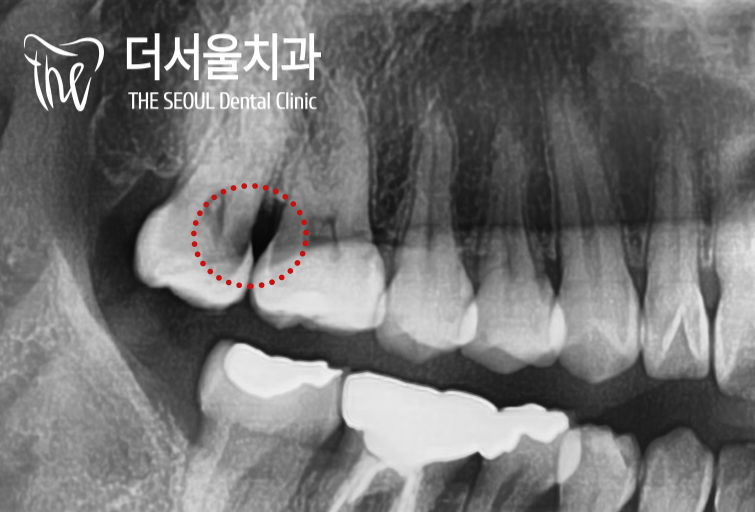

파노라마 촬영을 통해

불편감이 생긴 곳을 확인해봤더니

치아 사이가 검게 변해있네요.

구내 사진으로 확인해봤을 땐

별다른 특이소견이 느껴지지 않았는데요.

이것이 인접면 우식의 문제라 할 수 있죠.